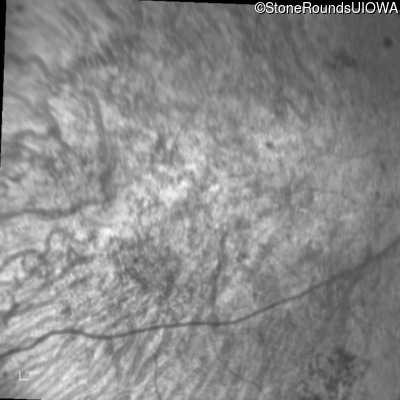

Age at visit: 41 years

This 41 year old man first came to medical attention at age 18 months when exotropia and amblyopia of his right eye were discovered. At age 11 vitreous strands and retinal vascular sheathing were seen. He has had poor night vision and constricted visual fields since his late teens. Later, at age 44 a traction retinal detachment was noted in his left eye and was treated with a scleral buckle.